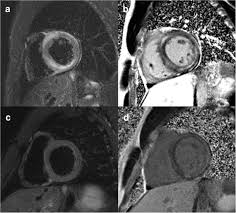

The Radiology Assistant Ischemic And Non Ischemic Cardiomyopathy

The Radiology Assistant Ischemic And Non Ischemic Cardiomyopathy from radiologyassistant.nl

More specifically, it is described as. Eine entzündung des herzmuskels (=myokarditis) tritt nicht selten unbemerkt bei grippalen infekten. Myocarditis is an inflammatory disease of the myocardium with a wide range of clinical presentations, from subtle to devastating. Mrt in der diagnose und monitoring neurodegenerativer erkrankungen. Myocarditis cardiosclerosis is a pathology in which parts of the myocardium involved in inflammation die and are replaced by connective tissue. Classified as idiopathic, these cases are attributed to genetic factors, viral myocarditis, and autoimmune mechanisms. Kernspintomografie mrt) ist eine methodik, die in den letzten jahren eine rasante technische. Journal of the american college of cardiology vol.

Ein in der mrt nachweisbares lge ist dabei nachweislich mit einer ungünstigeren prognose und einer erhöhten rate kardialer ereignisse assoziiert.